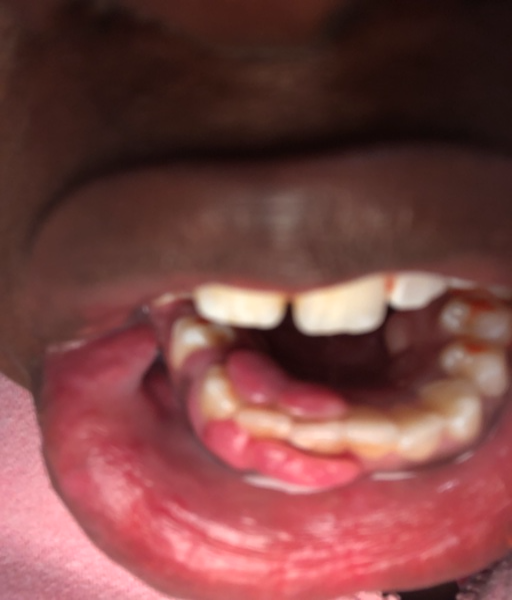

I need open bite sugery. i have had braces 2 times. The first time I finished it 18 months, then moved. My insurance changed so they said i would have to get a new referal to a oral surgon. So i went to the dentist and he said i should go to the orthodotist first and he knew a really good guy that was across the hall. The orthodontist said i would need braces again to align my teeth and close reopen bite before the surgery and would need a full round of braces and it would be 2500 after insurance. I was very surprised because my teeth looked very straight to me, but my mom said since the ortodontist said it i have to get braces again. so after i finished this my teeth looked exactly the same and i couldnt offers to do the sugery. now fast foward a few years. Im 21 now still on my moms insurance and i went to a new orthodontist to get a referral to a oral surgeon and The orthodontis said he didnt think braces could close my bite but I should get them any way to help align my teeth.

I have an open bite due to a tongue thrust I've had since I was a baby (I'm 22 now). My open bite has caused some issues like with trouble chewing, I have a slight lisp when I talk, I hate my smile and sometimes I find myself gasping for breath in...

Attached is an image of my condyles. Are they normal and healthy or Do you see any bone loss such as flattening or erosion of them? If there does appear to be some bone loss, how does this affect my bite and the appearance/position of my jaw?? Is...